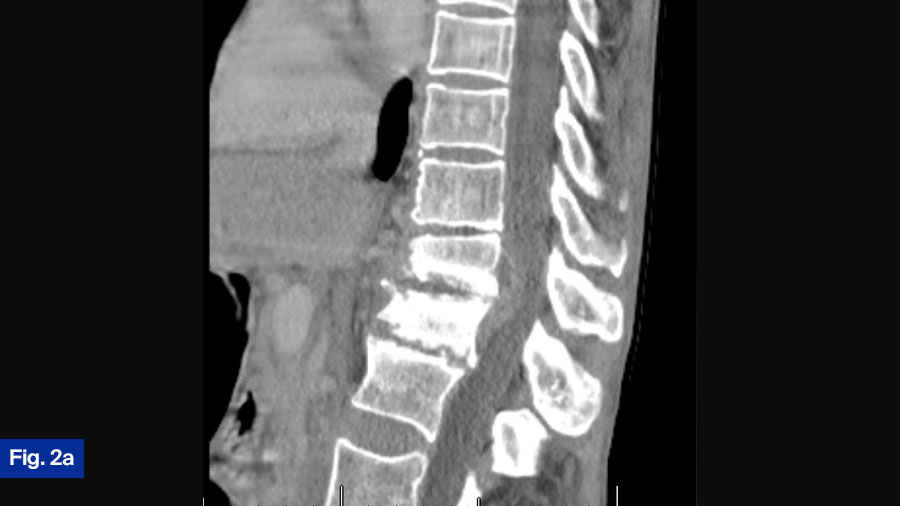

- CT scan: Demonstrated bony destruction and increased segmental kyphosis at T11-T12 (Figure 2a).

- MRI scan: Demonstrated a large ventral epidural phlegmon with moderate cord compression and thoracic hyperintensity with end-plate destruction (Figure 2b).

This patient is the most controversial case. The patient is neurologically intact but has spinal cord compression from an infection. Furthermore, this patient has significant bony erosions. I would treat this patient with surgical intervention in an urgent manner. Significant infection around the spinal cord can cause a spinal cord injury from a mechanical mechanism, but it can also cause vasospasm and spinal infarction. When looking at cervical epidural abscess, Alton et al (TSJ 2015) found a 75% failure rate of medical management largely due to a progressive neurologic deficit. While undoubtably there is some difference between the thoracic and cervical spine, I treat all patients with significant spinal cord compression from an infection surgically. At my institution, this patient would routinely have a lateral partial corpectomy utilizing autologous iliac crest autograft, followed by an instrumented posterior decompression and fusion, The patient would routinely get 6 weeks of IV antibiotics, however the use of suppressive antibiotics after the completion of IV is often variable. While there can be significant debate about the best surgical treatment, I think this patient should undergo surgical intervention.

This case is certainly controversial. At my institution, when such a case is presented at rounds, the room is divided regarding best treatment (initial medical treatment versus initial surgical treatment). Interesting and lively debates occur. This patient presents with a new diagnosis of discitis/osteomyelitis with some bony destruction and epidural abscess. He is neurologically intact and upright radiograph show the segment to be stable. Given this, I would admit the patient and attempt initial medical management. I would monitor response to treatment clinically as well as via laboratory inflammatory markers. Often, in the context of infection that receives adequate medical treatment, we see fusion of the segment. However, this patient will need to be monitored closely once discharged from the hospital with regular clinical assessments with upright radiographs as well as close monitoring by the infectious disease team. It is still possible that this patient requires surgical intervention. Given the growing international academic interest in this disease and the possible growing evidence that initial surgical intervention is best, it is possible that my approach to these types of cases will change as we reach consensus on best treatment.